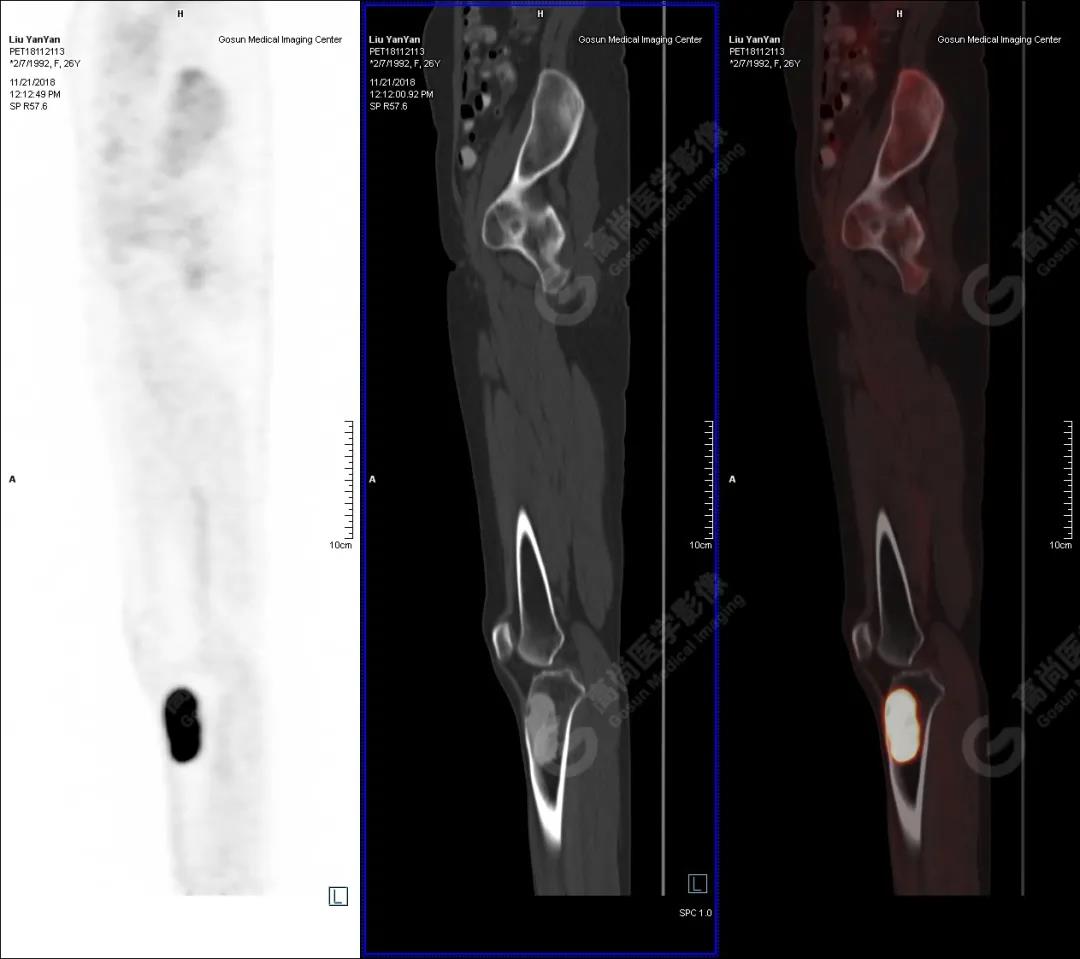

病史摘要

女性 ,26歲,右膝關節(jié)疼痛9個月,DR及MR檢查提示右側(cè)脛骨占位。既往無外傷史、無糖尿病、高血壓、肝炎、結(jié)核及手術史。

PET/CT檢查

PET/CT表現(xiàn)

右側(cè)脛骨上段髓腔內(nèi)見卵圓形塊狀高密度影,長徑與脛骨長軸平行,邊界清楚,密度欠均勻,CT值介于287.0Hu~425.0Hu,放射性攝取增高,SUV最大值為15.8,平均值為13.1。

PET/CT診斷

右側(cè)脛骨良性骨腫瘤樣病變,不除外非骨化性纖維瘤。

病理診斷

隨訪結(jié)果:活檢病理確診非骨化性纖維瘤。